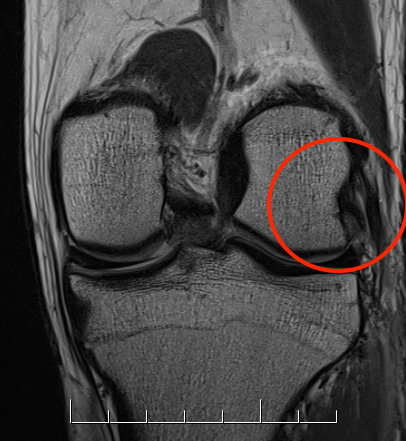

ACL / PLC / MCL

Coronal MRI of left knee demonstrating proximal MCL tear, with sagittal demonstrating complete disruption of ACL / PCL